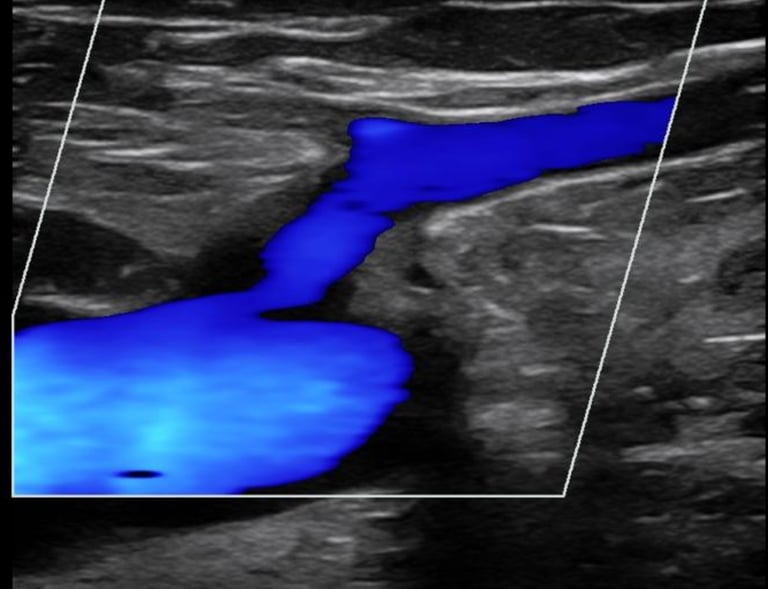

Galería

Imágenes de nuestros tratamientos en angiología y cirugía vascular.